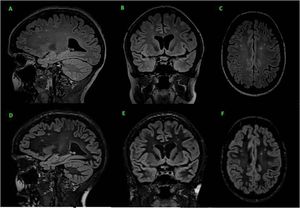

Fig 3D sagittal FLAIR (A) and multiplanar reconstruction in coronal (B) and axial (C) plane. 3D sagittal DIR (D) and multiplanar reconstruction in coronal (E) and axial (F) plane. 3D DIR provides higher sensitivity, therefore the MS lesions are better highlighted. Nonetheless, 3D DIR is acquired with lower spatial resolution and was more time consuming than 3D FLAIR.